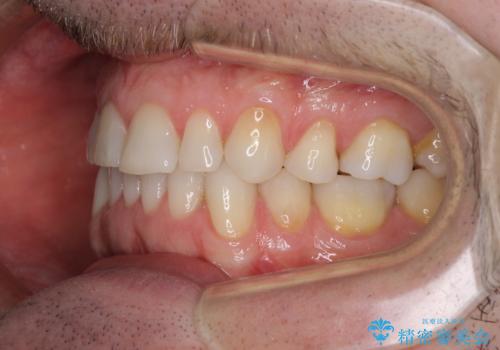

- 上下前歯の叢生を気にして来院された患者様です。

抜歯矯正をした後戻りということで、歯列不正はそれほど大きくなかったため、インビザライン・ライトを用いて矯正治療を行うこととしました。

前歯のデコボコが残っており、シミュレーション通りに動いていない部分がありましたが、再矯正であることやご本人の満足いくところまでデコボコが改善されたとのことで、治療を終了することとしました。